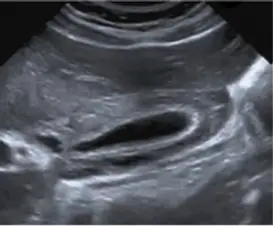

下圖為右上腹部超音波影像,其最可能的診斷為下列何者?

- 解剖構造定位:影像為右上腹部超音波,中央可見一長條形、內部呈無回音(anechoic)的囊狀液體構造,此為「膽囊(Gallbladder)」。

- 膽囊壁(Gallbladder wall)特徵:膽囊壁呈現明顯的均勻增厚(臨床定義正常膽囊壁應 3 mm)。特別引人注意的是,增厚的壁內呈現多層次、條紋狀(striated)的低回音與無回音帶(sonolucent stripe)。

- 病理徵象:這種典型的「雙層壁」或「光暈徑(halo sign)」外觀,代表液體堆積於膽囊壁的黏膜層與漿膜層之間,為典型的「膽囊壁水腫(Gallbladder wall edema)」影像表現。

- 管腔內(Lumen)狀況:膽囊腔內清澈,未見明顯的強回音(hyperechoic)亮點,後方亦無伴隨聲影(posterior acoustic shadowing),因此無明顯結石跡象。

- 軟組織特徵:未見不規則的軟組織腫塊向腔內突出或破壞膽囊壁原本的層次,因此排除惡性腫瘤的可能性。

綜合上述的影像分析,圖中位於右上腹的囊狀構造為膽囊,其最顯著的異常在於膽囊壁大幅增厚,並且在壁內出現低回音的層理結構(striated pattern / halo sign)。這代表著組織液滯留堆積在膽囊壁層內,是「膽囊壁水腫(Gallbladder wall edema)」的經典超音波表現。